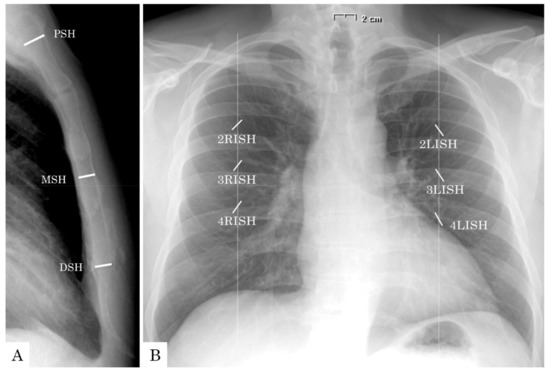

| PSH (mm) | 10.8 ± 1.7 | 12.7 ± 1.9 | <0.001 | 10.8 ± 1.7 | 12.6 ± 1.9 | <0.001 |

| MSH (mm) | 9.5 ± 1.7 | 10.3 ± 1.9 | <0.001 | 9.4 ± 1.8 | 10.3 ± 1.9 | 0.001 |

| DSH (mm) | 9.5 ± 1.8 | 10.3 ± 2.1 | 0.002 | 9.6 ± 1.9 | 10.3 ± 2.2 | 0.016 |

| iPSH (mm/m2) | 5.8 ± 0.9 | 6.7 ± 1.1 | <0.001 | 5.7 ± 1.0 | 6.6 ± 1.1 | <0.001 |

| iMSH (mm/m2) | 5.1 ± 1.0 | 5.4 ± 1.0 | 0.005 | 5.0 ± 1.0 | 5.4 ± 0.9 | 0.003 |

| iDSH (mm/m2) | 5.1 ± 1.1 | 5.4 ± 1.1 | 0.021 | 5.1 ± 1.1 | 5.4 ± 1.1 | 0.059 |